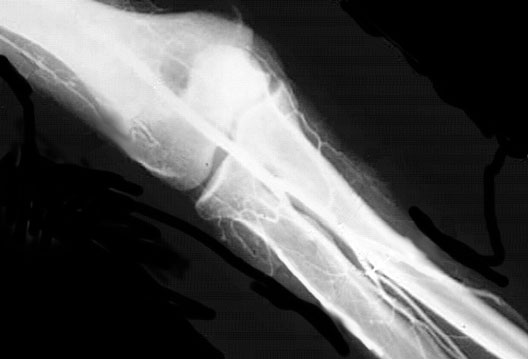

Elbow Collateral Vessels

1. Radial Collateral Artery

2. Brachial Artery

3. Radial Artery

4. Common Interosseous Artery

5. Ulnar Artery